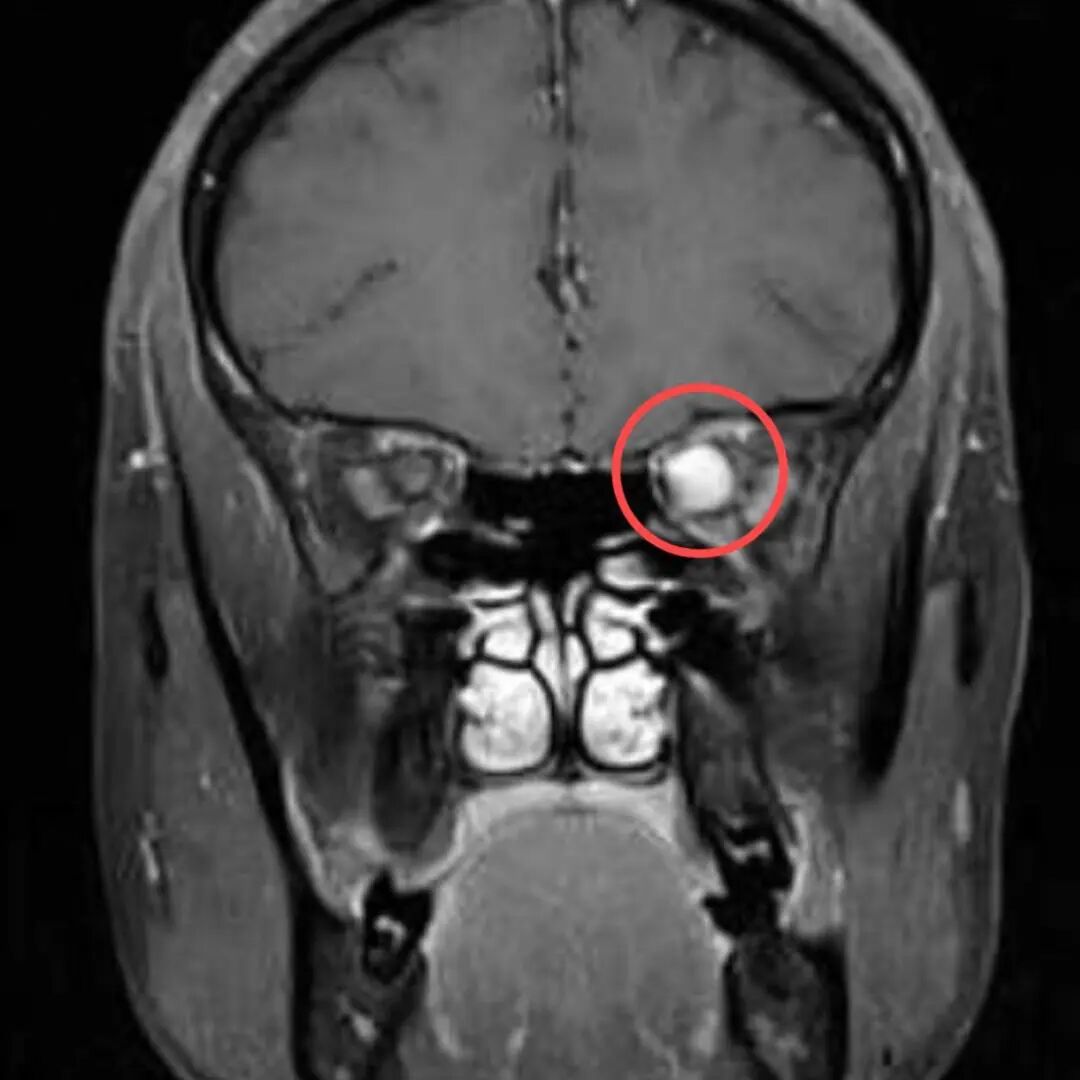

多年来,贵州航天医院各科室紧跟医学前沿,不断强技术、补短板,大力开展新技术、新项目,完成了许多高精尖、高难度、本地区“首例”的技术,填补了医院医疗技术空白,满足了群众日益增长的医疗需求。 案例分享 患者在两年前无明显诱因出现左眼胀痛、左眼视力下降等症状,由于当时患者自感不太严重,未予重视,随着时间的推移,症状逐渐加重,遂前来我院就诊,为更好的为患者进行诊治,收入了耳鼻喉科。经眼科查体显示:VOD(矫正视力)→1.0,VOS(矫正视力)→1.0,进行眼眶平扫+MRI检查后,初步诊断为:左眼球后脂肪间隙内占位,考虑良性病变,血管瘤可能。 考虑到患者病情复杂,耳鼻喉科组织眼科、麻醉科等科室开展了多学科联合会诊,对患者病情、既往病史等进行了全面深入的综合分析研讨,制定了鼻内镜下左侧鼻窦功能开放术+左侧眶内肿瘤切除术的方案,由于手术难度较大,在充分告知手术风险及并发症等相关信息后,患者及家属同意手术。经过充分的术前准备,耳鼻喉科借助经鼻内镜,成功通过鼻窦经由筛窦眶纸板、蝶窦外侧壁将肿瘤完整切除,最大程度地保护了眶内的血管、神经等重要组织。 术后,患者未出现视力减退、视野缺损等并发症,仅眶周稍青紫肿胀和轻微复视。患者2周后复查,复视症状、眶周青紫肿胀消除,术后MRI(眼眶平扫+增强扫描)显示左眶内肿物已消失。 该技术的开展,特别邀请了中山大学附属第一医院耳鼻喉科专家左可军教授莅临主刀,并对该技术的实施进行指导,已成功完成多例鼻眼相关内镜手术,解决了患者外出就医难、排队时间长、花费多等难题,让广大民众在家门口享受到了优质的医疗服务资源。 什么是鼻内镜下经鼻腔、 鼻窦进路眶内肿物切除术 眼眶是一个狭小的解剖间隙,结构复杂,功能重要,周围临近组织较多,含有许多重要结构,眶深部的肿瘤切除手术难度大,容易侵犯神经,出现视力丧失等并发症。随着眼-鼻相关学科发展和微创理念的深入,鼻内镜内侧开眶入路得到显著发展和应用,鼻内镜下经鼻腔、鼻窦进路眶内肿物切除术,具有微创、直视、并发症少等优势,目前已成为眶内肿物切除首选手术进路,主要应用于泪道系统疾病、眶骨折修复、眼眶内侧肿瘤切除、眼眶减压、海绵状血管瘤切除等。 鼻内镜下经鼻腔、鼻窦 进路眶内肿物切除术原理 手术基于先进的鼻内镜设备,通过鼻腔入路直接对眼眶及其毗邻区域进行操作,鼻腔与眼眶相邻,眼眶内侧壁主要由筛骨纸板构成,骨质菲薄,很容易经此进入眼眶,所以鼻腔可作为合适的手术通道,让操作更精准、更微创,同时,内镜下经鼻眼眶手术可利用该通道实现面部无切口。 鼻内镜下经鼻腔、鼻窦 进路眶内肿物切除术优势 ✔肿物可完整切除,较好的保护视力。 ✔可避免眼外部入路及经颅开眶入路的头面部切口。 ✔无脑组织的牵拉损伤,对眼内容物的牵拉损伤较小。 ✔经鼻切口外形无改变,术中组织结构放大、视野清晰,肿物分离更便捷。 贵州航天医院耳鼻喉科专家团队 左可军 中山大学 附属第一医院耳鼻咽喉科 贵州航天医院耳鼻喉科 特聘教授 医学博士 硕导 主任医师 临床擅长:鼻科、鼻眼相关外科、鼻颅底相关外科以及鼻变态反应科的临床和基础工作。 南方青年鼻科联盟创始人,担任中国医师协会耳鼻咽喉科分会整形美容学组委员、海峡两岸医药卫生交流协会眼科学专业委员会眼科内窥镜微创手术学组委员、广东省精准医学应用学会头颈肿瘤分会副主委、广东省中西医结合学会耳鼻咽喉科分会副主委、广东省眼健康协会眼与全身疾病专业委员会常委。获得国家二级运动员和南粤优秀研究生称号,2018年荣获“广东医院最强科室之实力中青年医生”,2020年荣获全国卫生健康系统抗疫先进集体、中国医师协会耳鼻咽喉头颈外科分会抗疫先进个人,2021年荣获广东省科技进步一等奖,2023年荣获第七届“羊城好医师”。 张光进 耳鼻喉科主任 副主任医师 临床擅长:对耳鼻喉头颈常见病的诊治具有丰富的临床经验,擅长鼻内镜、耳内镜、耳显微、头颈咽喉部肿瘤及眩晕手法复位等的诊疗。 曾先后前往第三军医大学西南医院、复旦大学耳鼻喉科医院、上海新华医院及北京友谊医院进修学习;遵义市医学会常务委员;主持及参与级科研课题2项,发表专业论文10余篇。 陈维信 耳鼻喉科 主任医师 临床擅长:对耳鼻喉科常见疾病的诊治具有丰富的临床经验,擅长耳、鼻、喉及头颈部位的手术。 曾先后前往上海交通大学附属仁济医院耳鼻喉-头颈外科、北京大学人民医院耳鼻喉-头颈外科参加鼻内镜外科进修学习。中国睡眠研究会委员,贵州省医学会耳鼻喉-头颈外科学分会委员,贵州省耳鼻喉-头颈外科学会理事,贵州省医学会变态反应学分会委员,贵州省防聋治聋技术指导组专家,遵义市耳鼻喉科分会副主任委员,遵义市医疗事故鉴定专家库成员;主持省部级科研课题2项,发表专业论文20余篇。 秦 晋 耳鼻喉科 副主任医师 临床擅长:对耳鼻喉科常见疾病的诊治具有丰富的临床经验,擅长耳、鼻、喉及头颈部位的手术。 遵义市医学会常务委员;曾先后在第三军医大学西南医院、湖南湘雅鼻颅底培训班进修学习。 贵州航天医院耳鼻喉科简介 基本情况 贵州航天医院耳鼻喉科拥有一支经验丰富、技术精湛的医疗团队,共有医师9名,其中副高级以上专家5名,医学硕士2名,开放床位20张,拥有德国WOLF鼻窦内窥镜系统、日本奥林巴斯电子喉镜、奥林巴斯电子鼻咽镜、丹麦临床听力监测设备、声导抗仪、听觉诱发电位、耳声发射仪、美国杰西低温等离子治疗仪、杭州好克鼻窦内窥镜系统、鼻动力系统、耳显微镜、耳用电钻、微波治疗仪等先进设备。 专科特色 (一)耳部疾病 耳内镜下胆脂瘤切除术、III型鼓室成形术+人工听骨听骨链重建术。 (二)鼻部疾病 内镜下鼻息肉切除术、鼻窦功能开放术。 (三)咽喉疾病 内镜下扁桃体、腺样体低温等离子切除术。 (四)交叉学科 1.经鼻内镜下眶内肿瘤切除术 2.经鼻内镜下鼻腔泪囊吻合术 诊疗范围 (一)常见耳疾的诊断和治疗:中耳炎、耳聋、耳鸣等。通过各种耳科检查手段,如耳镜检查、听力测试和耳脑干听觉诱发电位检查等,准确诊断患者病情,制定个性化治疗方案。 (二)鼻炎、鼻窦炎、鼻出血等鼻科疾病的诊断和治疗:采用微创技术,如鼻内窥镜检查、低温等离子手术等,为患者提供有效的治疗方案。 (三)喉炎、声带息肉、声带白斑等喉科疾病的诊断和治疗:通过声带电子镜、喉镜等设备,准确判断患者的喉部病变,为患者提供精准的治疗方案。 (四)鼻眼、鼻颅底相关手术。